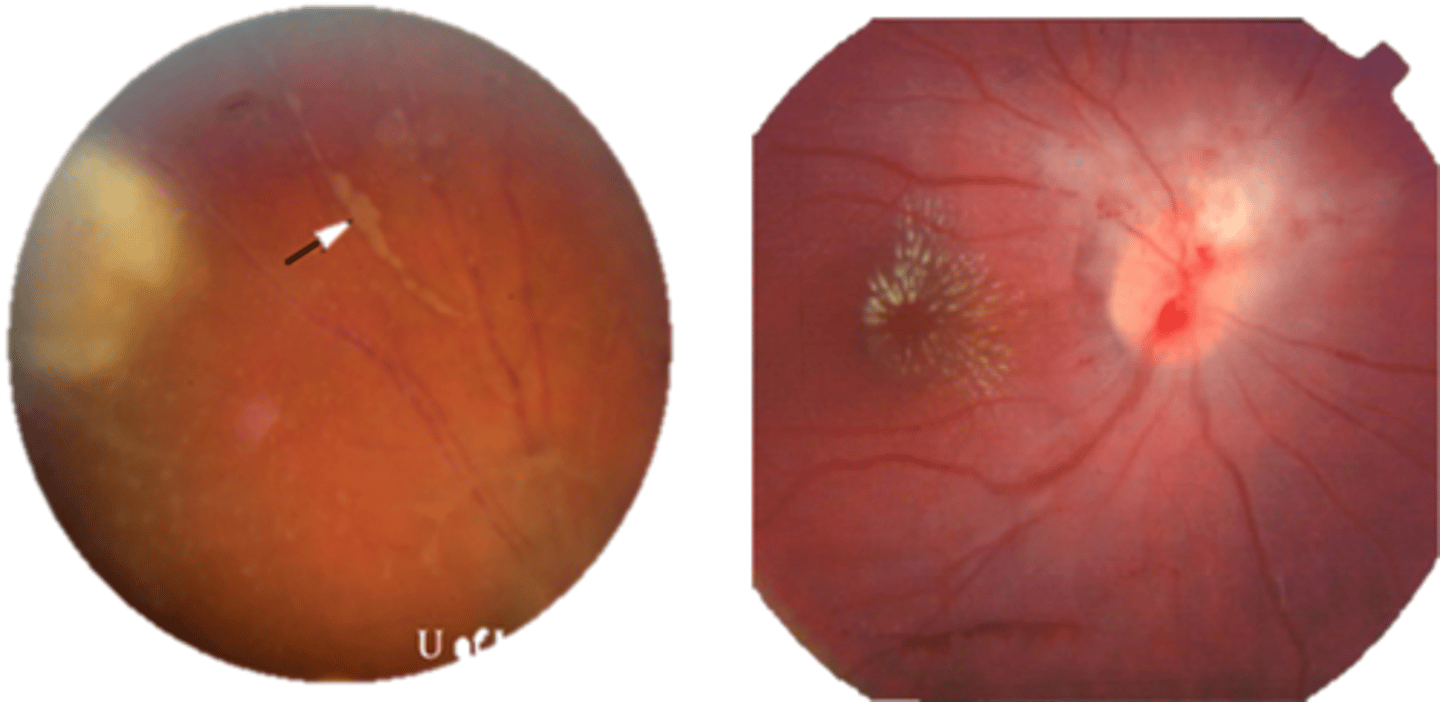

What findings of toxoplasmosis are seen here?

retinal vasculitis

exudative scar

focal, hazy vitritis and retinitis

What findings of toxoplasmosis are seen here?

latent scars